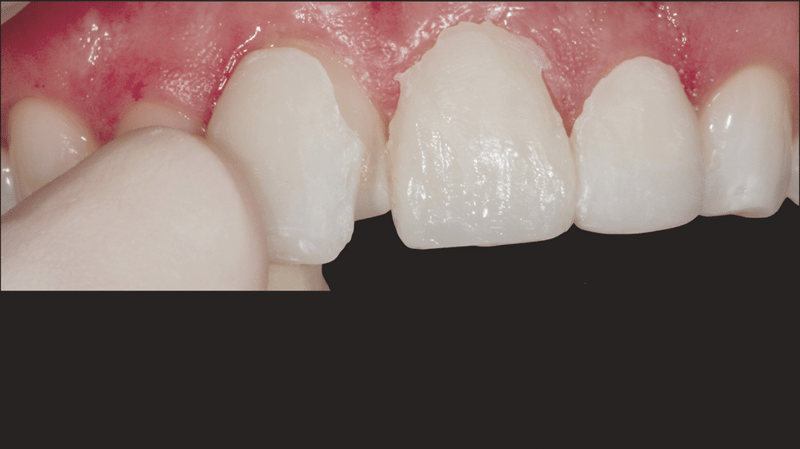

A young woman in her 20s, burdened by the discoloration of her upper anterior teeth from past trauma, came to Dr. Jaleena Fischer-Jessop, DDS, MBA, searching for a solution that would restore her smile. The patient was treated with a conservative and cost-effective solution: no-prep direct-bonded composite veneers. Dr. Fischer-Jessop chose this method to mask the discoloration and match the patient’s upper teeth with the lower anteriors—avoiding the need for more invasive procedures like implants or costly lab processed veneers. The shades B1D and Enamel White (EW) were selected to lighten the teeth and Transcend™ composite’s Universal Body (UB) shade was used to ensure the margin blended naturally into the cervical areas.

- Patient Background: A female patient in her 20s with a history of trauma to her upper anterior teeth. Despite the trauma, the teeth remained stable, so implants were not necessary.

- Esthetic Concerns and Financial Considerations: The patient expressed concerns about the appearance of her teeth and was financially constrained. Given the circumstances, no-prep direct-bonded composite veneers were chosen as the solution.